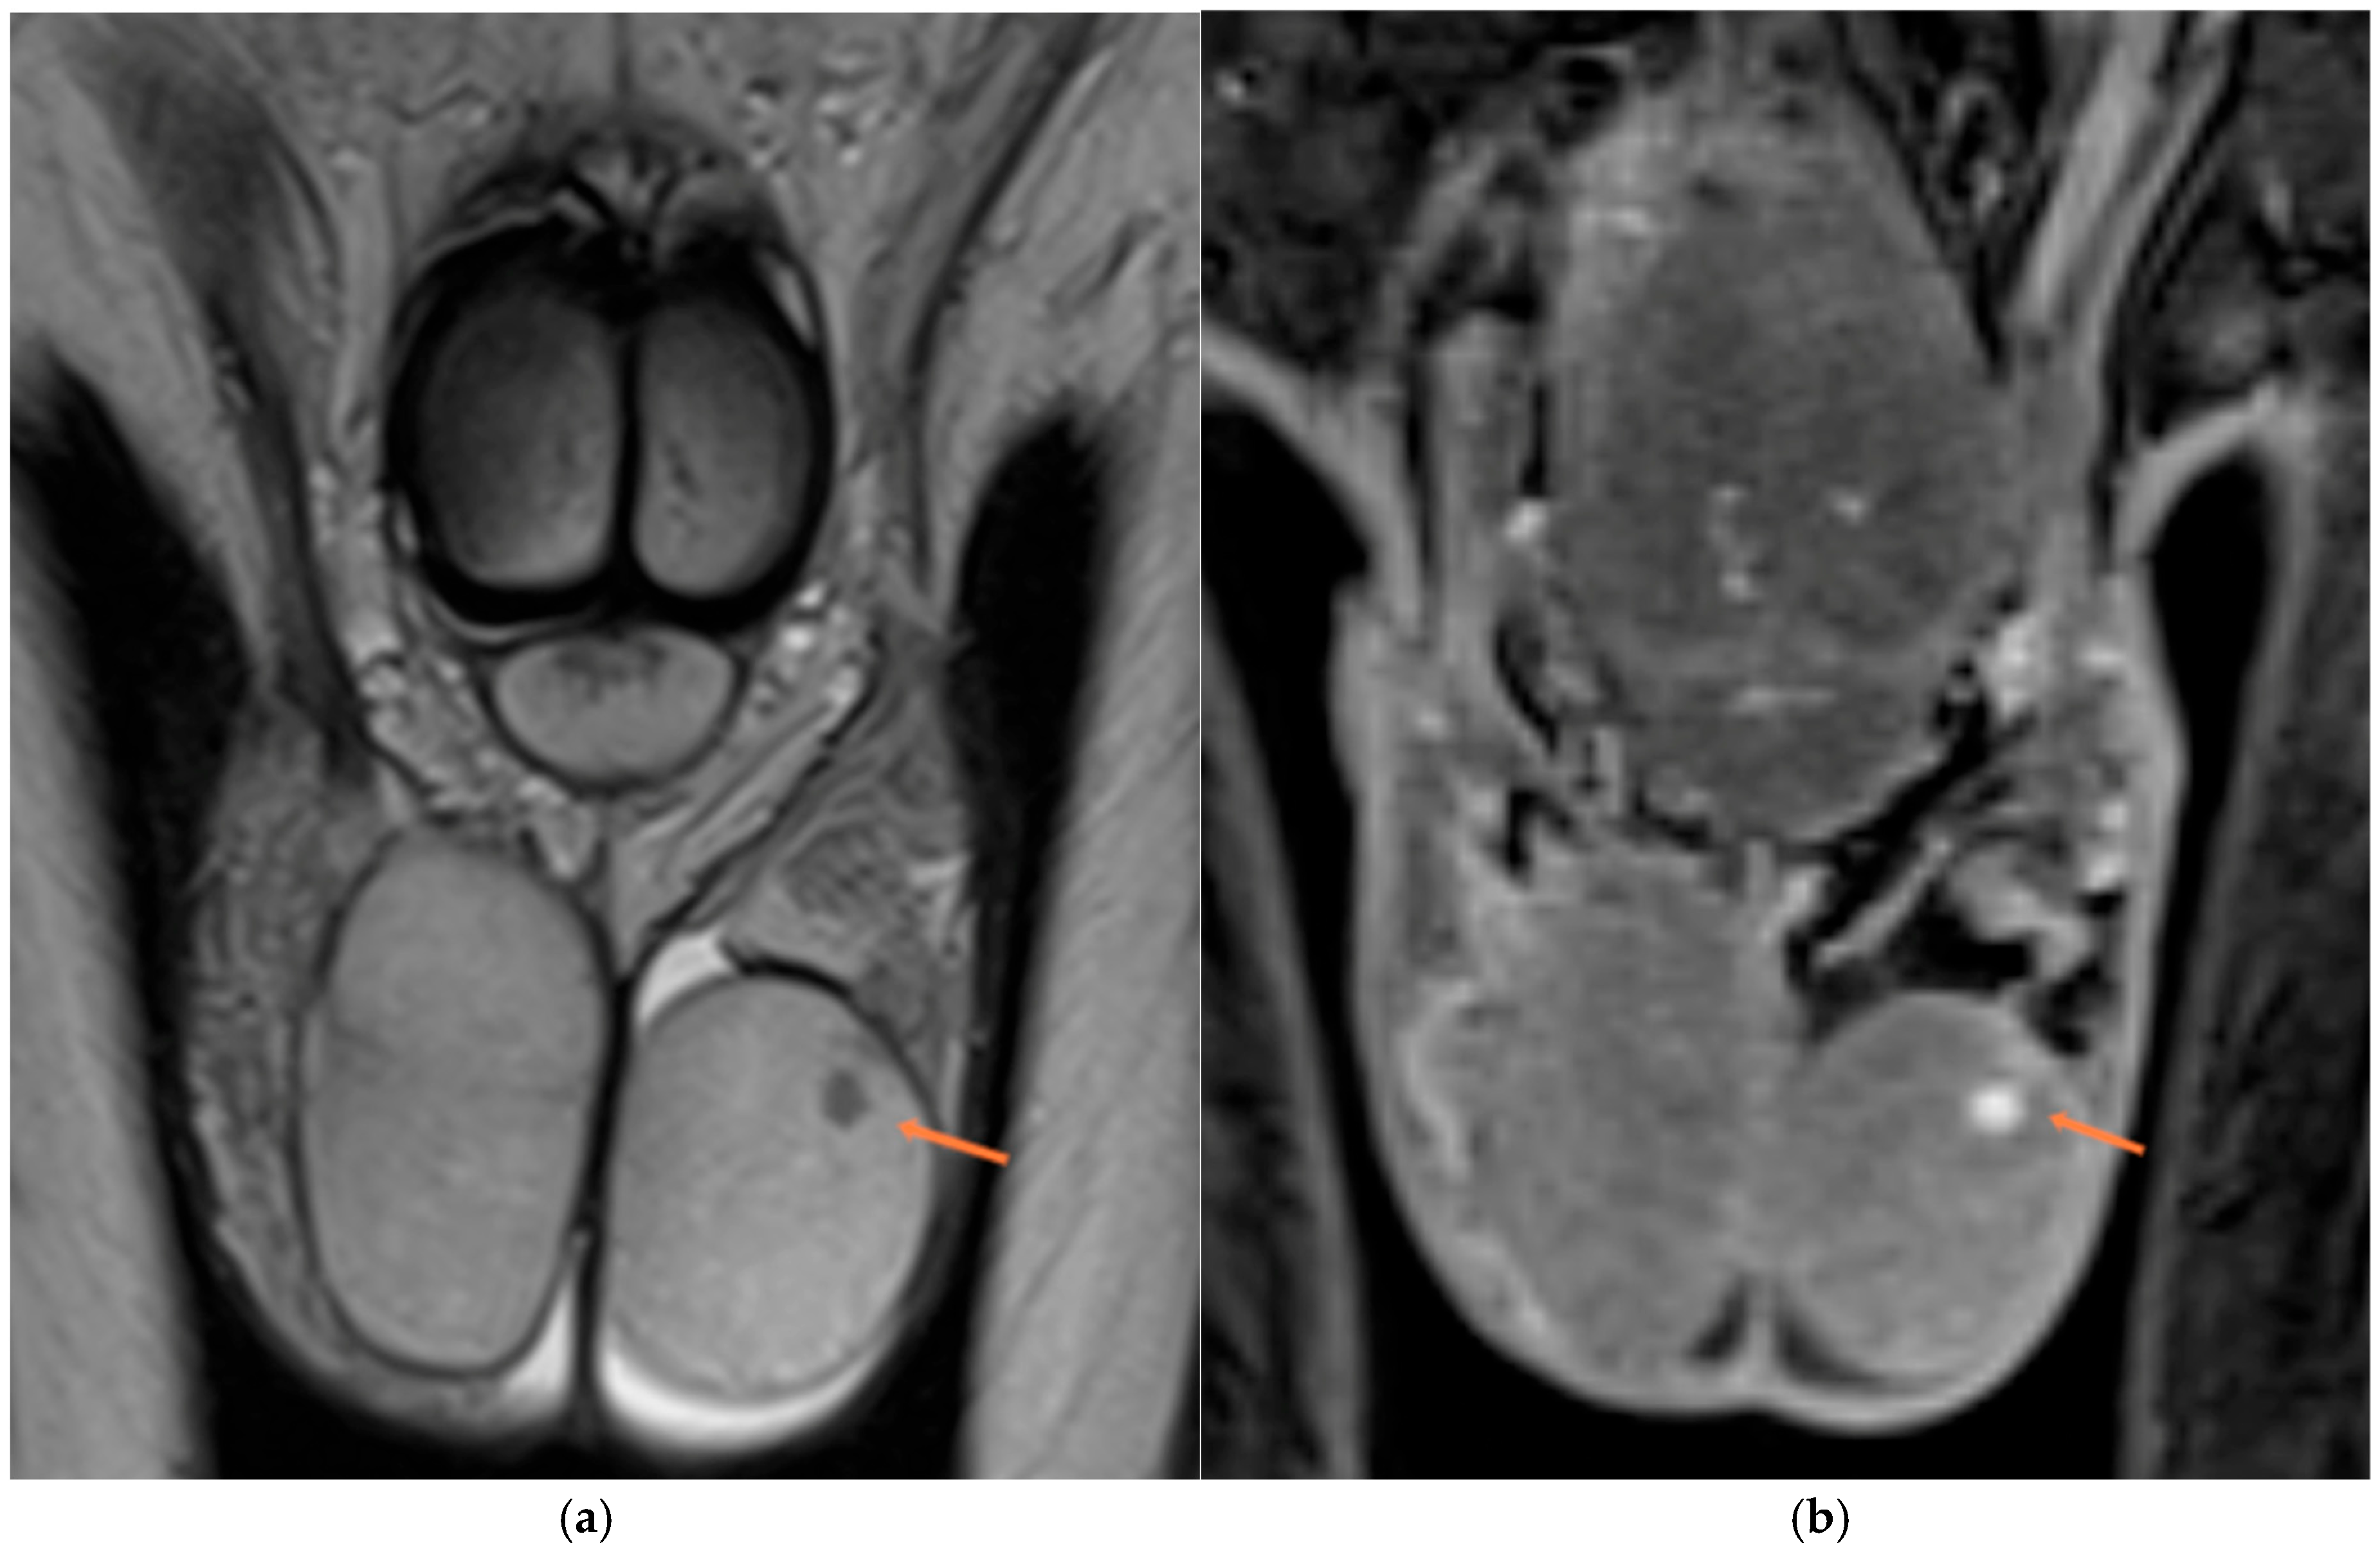

3.3.2. Paratesticular and Extratesticular Masses

3.4. Infertility